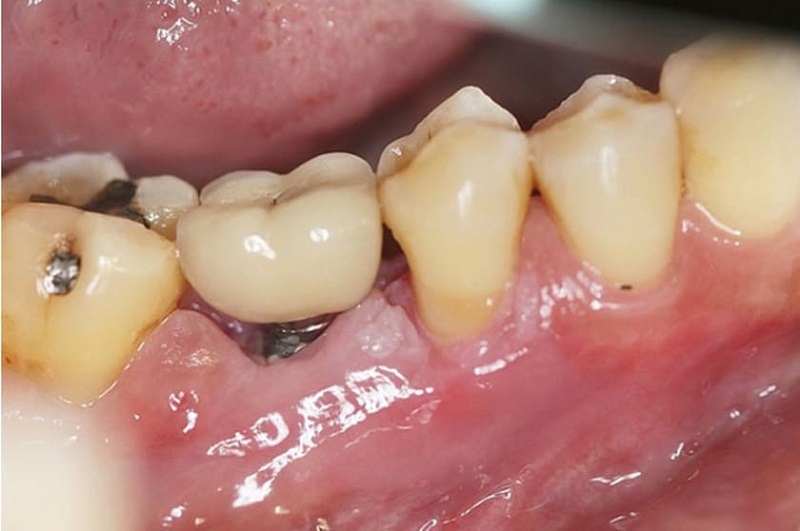

Nếu Tùng Anh trồng răng khi viêm nha chu chưa được điều trị triệt để có thể khiến Implant khó tích hợp với xương, dễ bị viêm quanh trụ, tiêu xương nhanh và tăng nguy cơ đào thải.

- Trụ Implant khó tích hợp với xương: Nếu tiến hành cấy Implant khi bệnh nha chu chưa được kiểm soát triệt để, môi trường vi khuẩn trong khoang miệng sẽ tiếp tục phát triển và xâm nhập vào xương hàm, làm cản trở quá trình liên kết giữa trụ Implant và xương, gây đau nhức, viêm nhiễm kéo dài.

- Giảm tỷ lệ thành công của Implant: Nếu Tùng Anh bị viêm nha chu nặng, mô nướu và xương hàm thường không còn đủ khỏe mạnh để nâng đỡ trụ Implant. Vì vậy, tỷ lệ thành công của ca cấy ghép sẽ thấp hơn so với người có sức khỏe răng miệng tốt.

Viêm nha chu nặng có thể gây đào thải trụ trồng răng